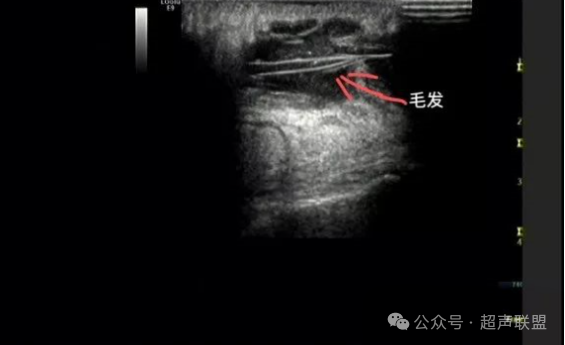

7.毛发样强回声是该病的重要特征性表现。该病例声像图内可见线样强回声,为毛发,故诊断为藏毛窦。